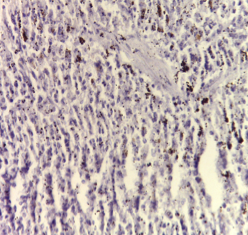

Immunohistochemical investigations

Optical micrograph for immunohistochemical staining of negative control spleen tissue using an antibody against VEGF showed positive immunoreaction for VEGF (fig. 2a). Optical micrograph for immunohistochemical staining of DMN group showed negative immunoreaction for VEGF in splenic tissue (fig. 2b). Furthermore, an optical micrograph for immunohistochemical staining of splenic tissue sections of PRP or those administered orally with Qeurcetin showed positive immunoreaction for VEGF in splenic tissue (fig. 2c and 2d respectively).

Fig. 2(a-d): Immunohistochemical determination using antibody against VEGF in splenic tissue, (a) Normal control showed positive reaction, (b) DMN group showed negative reaction, (c) PRP group showed positive reaction and (d) Qeurcetin group showed positive reaction (a-d X100)